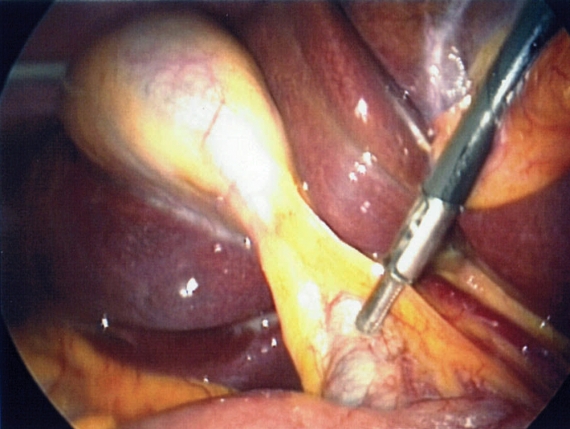

La colecistectomía temprana es ampliamente recomendada en el manejo de la colecistitis aguda debido al alto riesgo de recurrencia de los ataques agudos y las complicaciones asociadas. Esta intervención quirúrgica, generalmente realizada de manera laparoscópica, se considera crucial dentro de las primeras 24 horas después del ingreso hospitalario para pacientes diagnosticados con colecistitis aguda.

La colecistectomía laparoscópica es el procedimiento estándar preferido debido a sus ventajas en términos de recuperación postoperatoria. Sin embargo, entre el 2 % y el 15 % de los casos pueden requerir la conversión a una colecistectomía abierta debido a dificultades técnicas o complicaciones intraoperatorias que no pueden manejarse de manera adecuada con la técnica laparoscópica.

Comparativamente, los beneficios de realizar la colecistectomía dentro de las primeras 24 horas son significativos. Se ha documentado que esta práctica se asocia con una estancia hospitalaria más corta para los pacientes, lo cual no solo reduce los costos hospitalarios sino que también mejora la experiencia del paciente al acortar el tiempo de recuperación. Además, la colecistectomía temprana puede resultar en una mayor satisfacción general del paciente debido a la resolución rápida de los síntomas agudos y la prevención de futuros episodios dolorosos.

Aunque existe la posibilidad de un aumento en las tasas de complicaciones quirúrgicas inmediatas debido a la urgencia del procedimiento, como la perforación vesicular o lesiones de la vía biliar, los estudios sugieren que los beneficios de la colecistectomía temprana superan estos riesgos. Los resultados adversos quirúrgicos pueden manejarse eficazmente con el monitoreo cuidadoso durante la intervención y la atención postoperatoria adecuada.